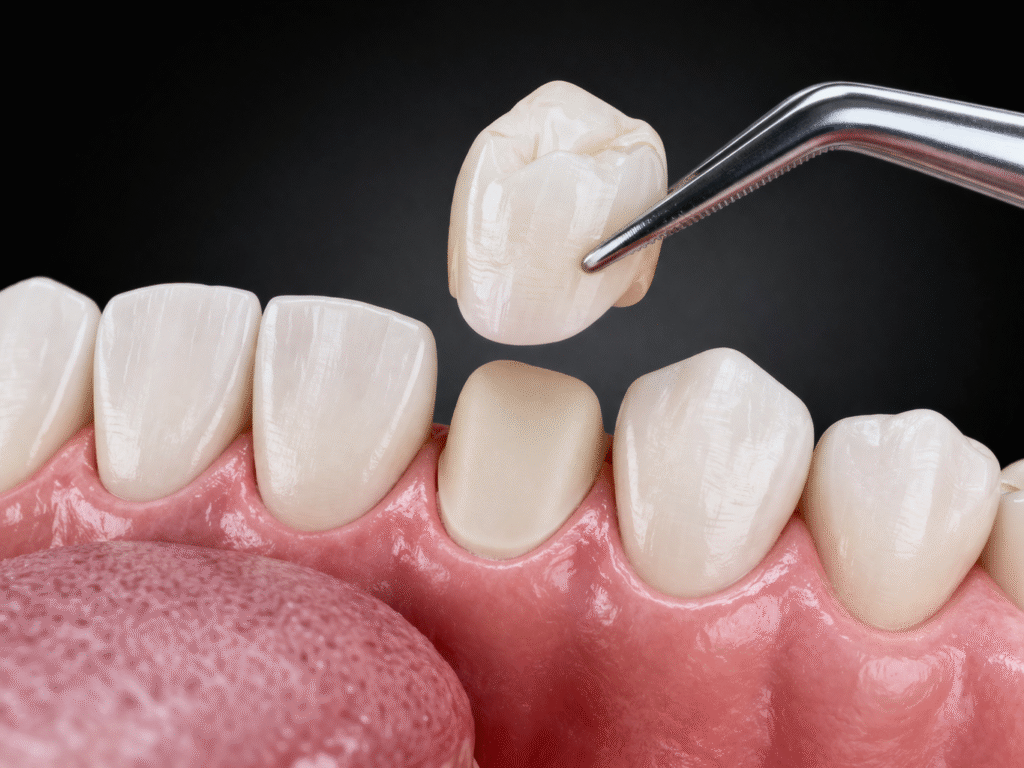

Estetik diş hekimliğinde kullanılan materyaller arasında öne çıkan zirkonyum, hem dayanıklılığı hem de doğal görünüm sunabilmesi sayesinde modern uygulamaların temelini oluşturur çünkü metal destekli kaplamalarda zamanla görülebilen gri yansıma, diş eti kenarında koyu renklenme veya yapay görünüm gibi dezavantajlar zirkonyum altyapılı kaplamalarda büyük ölçüde ortadan kalkar. Antakya’da zirkonyum diş kaplama yaptıran hastalar için bu özellik, özellikle ön diş bölgesinde oldukça önemli bir avantaj sağlar çünkü ışık geçirgenliği sayesinde kaplamalar doğal diş minesine benzer bir estetik sunar ve bu da dişlerin yapay görünmesini engeller. Bununla birlikte zirkonyum materyali yalnızca estetik açıdan değil, biyolojik uyum açısından da güçlü bir yapı sunar; diş eti ile uyumlu olması sayesinde uzun vadede diş eti problemlerinin oluşma riskini azaltır ve bu durum tedavinin kalıcılığını doğrudan etkiler.

Zirkonyum diş kaplama Antakya süreci, detaylı muayene ile başlar ve ardından planlama, hazırlık, ölçü alma ve prova aşamaları ile devam eder çünkü bu aşamaların her biri tedavinin başarısını doğrudan etkiler. Dişlerin hazırlanması sırasında gereksiz madde kaybından kaçınılmalı ve mümkün olan en konservatif yaklaşım benimsenmelidir çünkü diş dokusunun korunması uzun vadeli sağlık açısından önemlidir. Ölçü alma aşamasında yapılan küçük hatalar bile kaplamanın diş ile uyumunu etkileyebilir ve bu durum ilerleyen süreçte hassasiyet veya uyumsuzluk problemlerine yol açabilir. Antakya’da zirkonyum diş kaplama uygulamalarında prova aşaması ise estetik ve fonksiyonel uyumun birlikte değerlendirildiği kritik bir adımdır ve bu aşamada yapılan düzenlemeler, tedavinin başarısını belirleyen en önemli faktörlerden biridir.